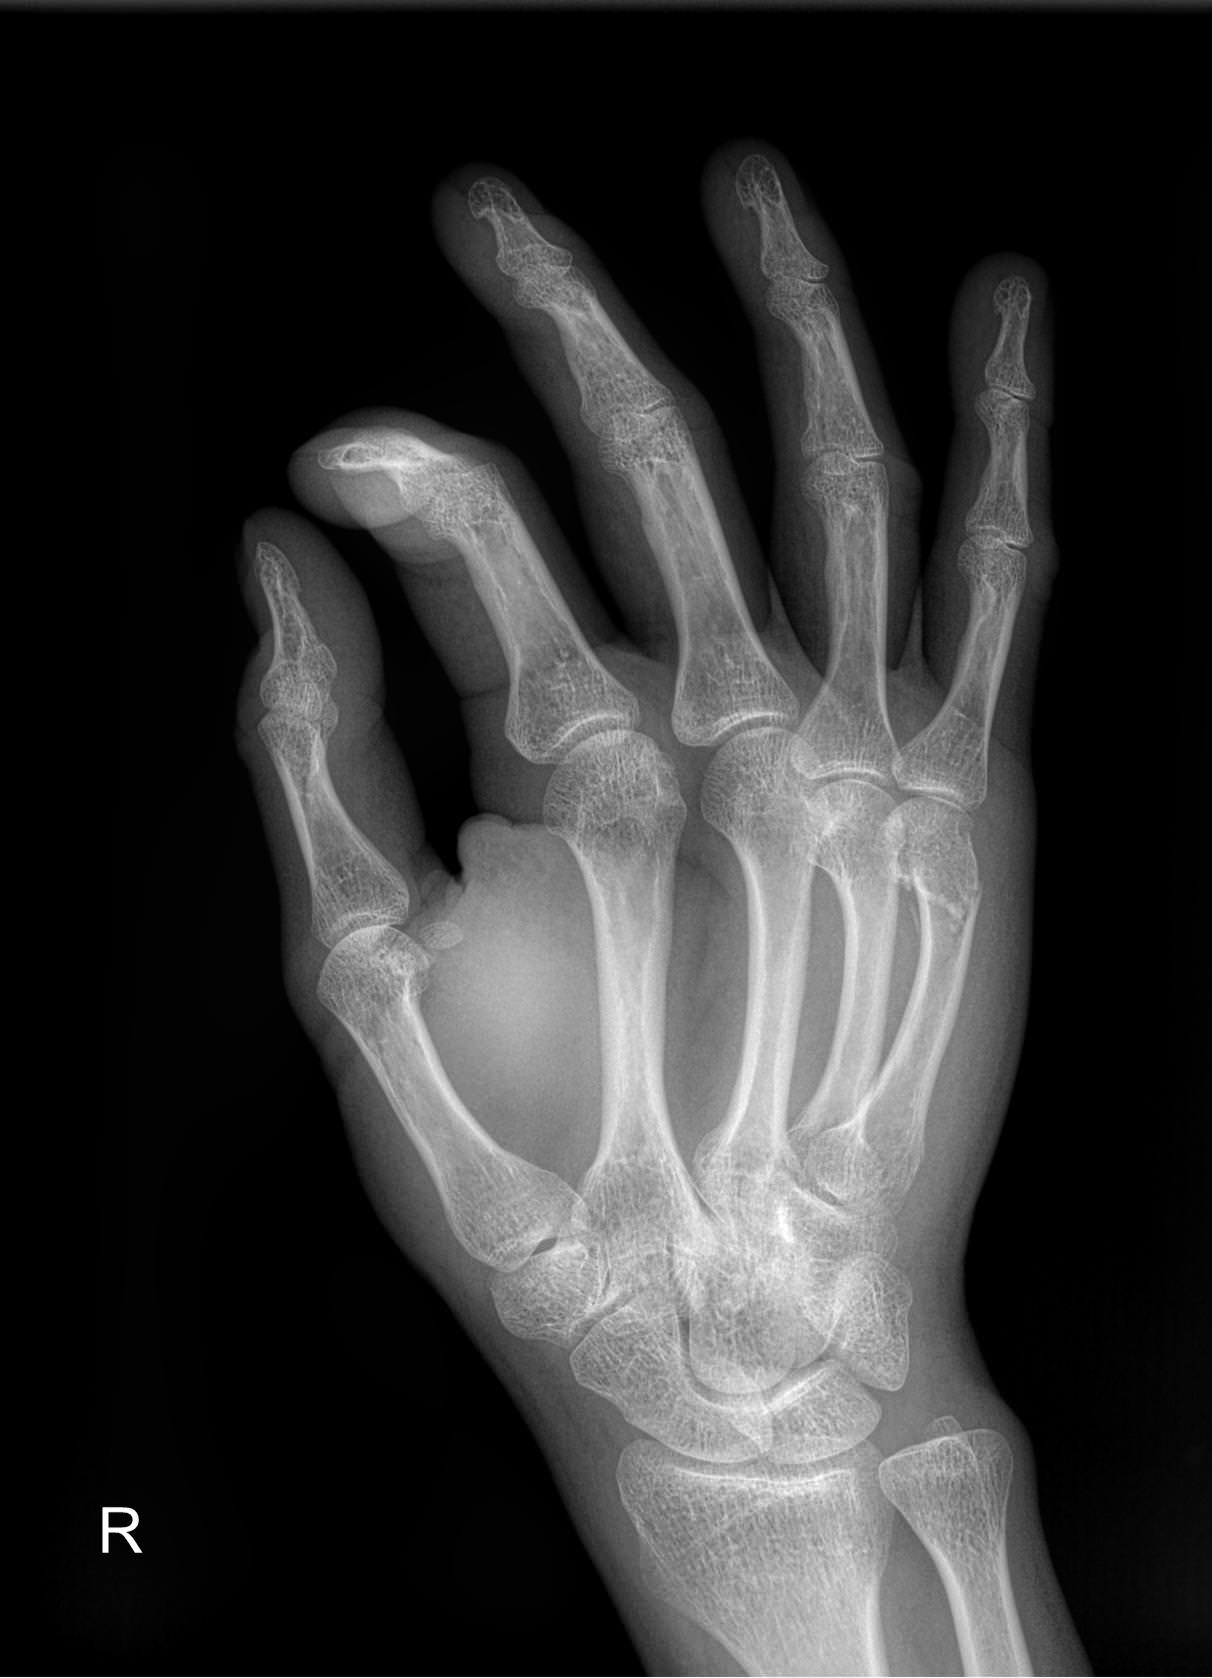

Ладонь и пальцы ― один из самых сложных участков в организме человека. Здесь сосредоточено огромное количество мелких суставов, каждый их которых может воспалиться или быть поврежденным в результате профессиональной деятельности и спорта. Изменения, связанные с возрастом или хроническим заболеванием, также влияют на состояние и функции кистей рук.

Болезни кистей серьезно ухудшают качество жизни, поэтому такие патологии редко игнорируют. Однако их симптомы схожи, что требует тщательной диагностики перед тем, как выбрать метод лечения. Одно из базовых исследований ― рентгенологическое. Это простое, быстрое, информативное и недорогое исследование. Современное цифровое оборудование, которое используют в клинике «Доступная медицина», во время процедуры несет минимальную дозу облучения. Это делает рентген практически безопасным методом обследования.

Что показывает рентген кисти

В протоколе рентгенолог описывает изменения, которые произошли в области исследования:

• Состояние суставных щелей;

• Соответствие друг другу суставных поверхностей;

• Патологические изменения поверхности суставов;

• Состояние костной ткани ― травматические и дегенеративные деформации;

• Возможные новообразования;

• Мягкие ткани.